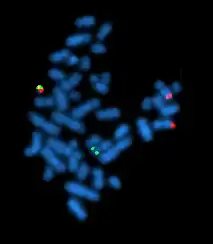

| A metaphase cell positive for the bcr/abl rearrangement using FISH | |